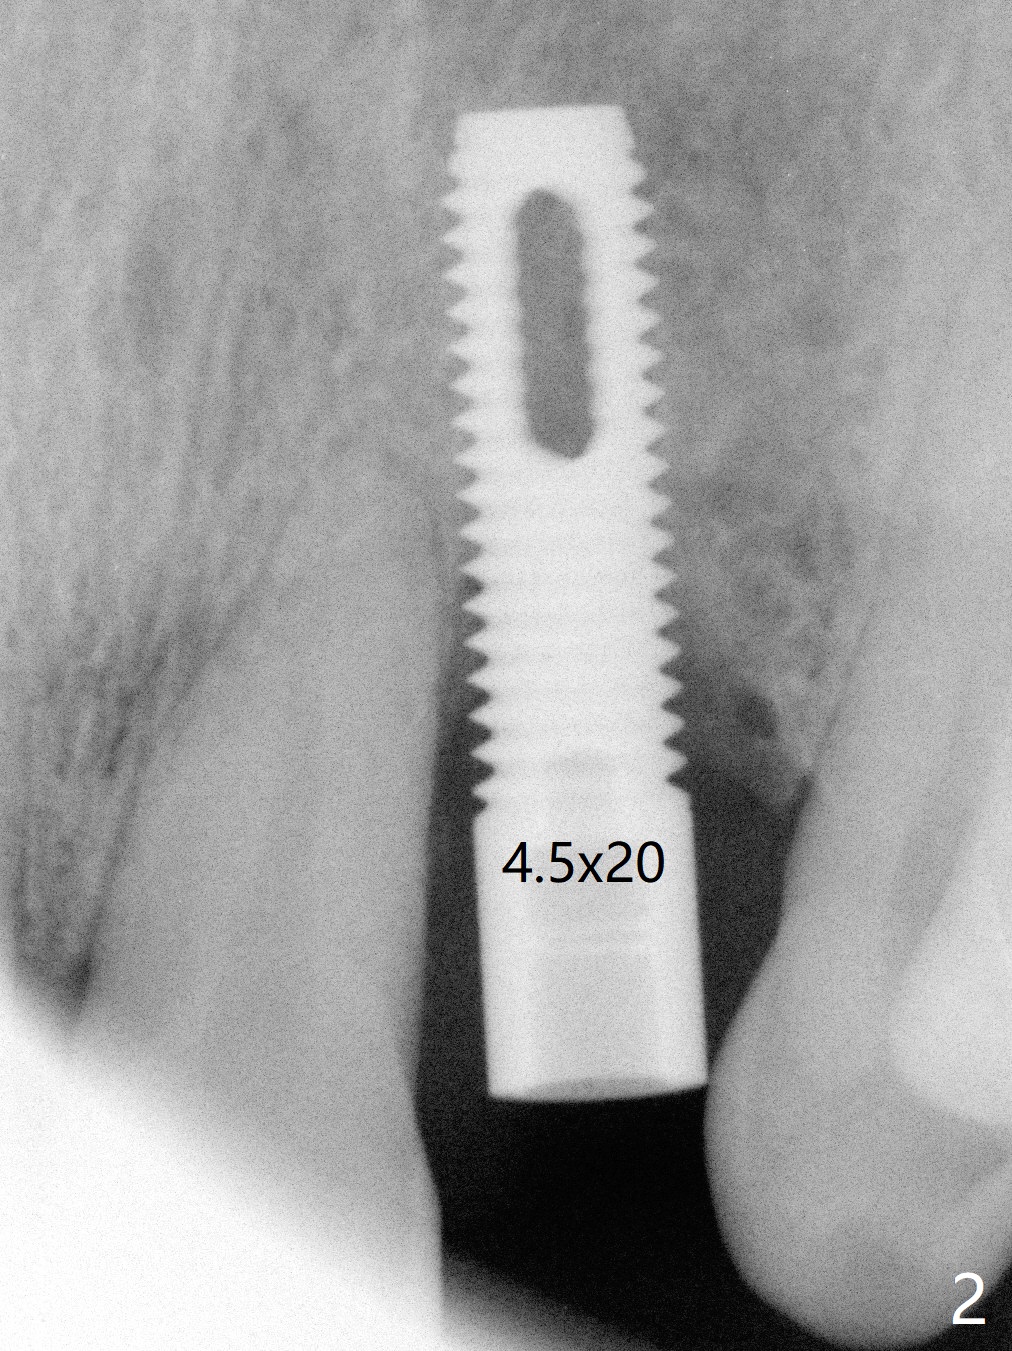

A 61-year-old man has chronic periodontitis and bruxism (Fig.1). Immediately after extraction and Clindamycin socket treatment, osteotomy is initiated with a 2 mm pilot drill at 20 mm in the lower 1/3 of palatal wall with normal saline irrigation, followed by 2.5-4 mm reamers at 20 mm (bone saved, Type III bone). A screw Implant (4.5x20 mm) is placed (45-50 Ncm, Fig.2). The root measurements were B-L 6.5 mm and M-D 5 mm. Autogenous bone is mixed SynthoGraft (size 50-500) ~ .3 g and blood. A 3.5x5 mm abutment is immediately cemented with an immediate provisional. There is positive bone growth 3 years post cementation (Fig.3 *). There is no buccal plate bone resorption 3 years 2 months post cementation (Fig.4 CT).